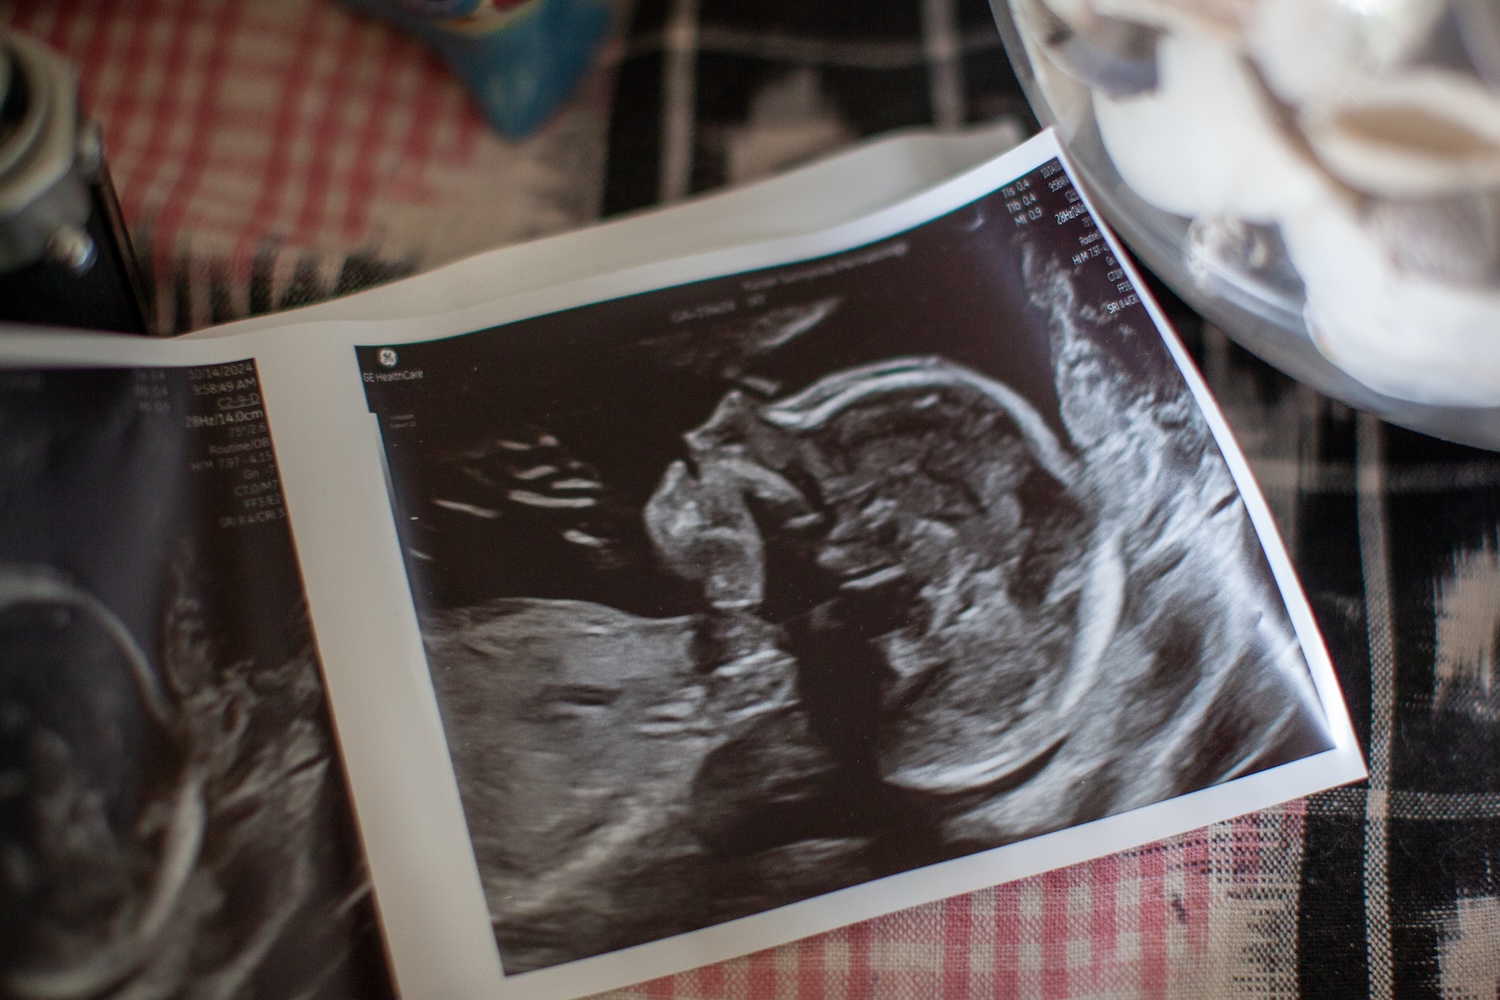

Despite the flashes, most of the details of this time are lost to me. Did my brain bury them because the emotional weight was too much to bear? Or maybe, once our baby was born, a kind of blissful postpartum amnesia took hold, the elation of finally having a child sanding off the most jagged edges of the pain. Maybe our path seems less treacherous and depressing when you know that at the end of it lay what we always wanted: a baby.